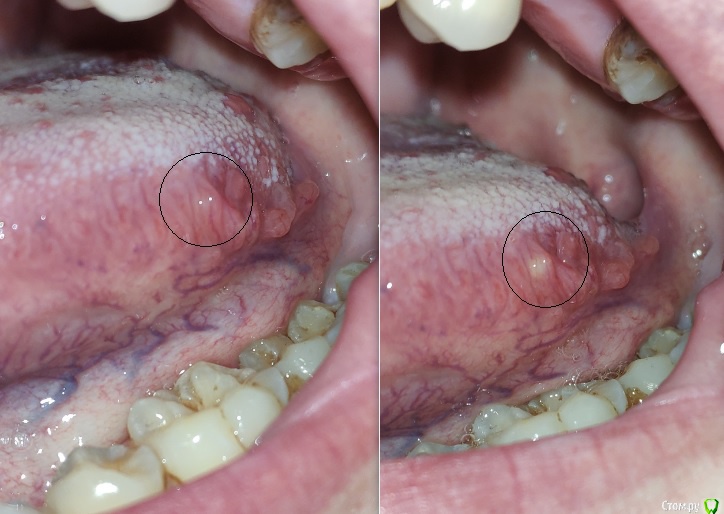

posman Опубликовано 8 октября, 2018 Поделиться Опубликовано 8 октября, 2018 (изменено) Здравствуйте! Просьба проконсультировать касаемо возможной "природы" образований на фото.Наросты выявлены около 10 лет назад при очередном осмотре у ЛОР-врача.Симметричны с двух сторон языка, на левой стороне более выражены. Динамика роста отсутствует, в последние 2 месяца отмечена некоторая болезненностьс левой стороны у корня языка, отдающая в область нижнего 8го зуба и небной дужки(ноющий дискомфорт в т.ч. при употреблении пищи). В ночное время боль отсутствует. За последнюю неделю слева появилось небольшое желтое "включение", м.б. нагноение (видно на фото в динамике). В течении двух месяцев посетил трех лоров, чл-хирурга и двух специалистов по слизистым,выполнено МРТ мягких тканей шеи (без патологий).Фарингоскопия также патологий не выявила, ЧЛХ связал болезненность с 8м зубом, который до конца не прорезалсяи имеет десневой карман. Один специалист по слизистым поставил глоссит, второй коллега указал на вероятную глоссалгию.Касаемо "наростов", мнение стоматологов - физиология и сосочки языка. ЛОРы - лимфоидная ткань язычной миндалины.За время "истории" прошёл противогрибковую терапию (флюкостат), антибиотики не употреблял. бак-посев не выявил патогенной микрофлоры, ОАК месячной давности в пределах нормы. По сути, интересует три момента:1. Природа наростов. Понимаю, что точно может показать только гистология, но хотя бы визуально. 2. Возможная связь дискомфорта с зубом мудрости, карманом или др.неврологической причиной. 3. "Гнойник" на наросте, что делать, как лечить. Фото языка и 8ки, а также снимок ОПТГ прилагаю. Буду признателен за комментарии. Изменено 8 октября, 2018 пользователем posman Ссылка на комментарий

posman Опубликовано 11 октября, 2018 Автор Поделиться Опубликовано 11 октября, 2018 Доброго времени суток! Уважаемые участники, Просьба оценить фото, что за воспаление желто-белого цвета под слизистой и что можно предпринять, т.к. обратиться к врачу смогу только через неделю.Болевых ощущений не вызывает. Заметил 4 дня назад. Ссылка на комментарий